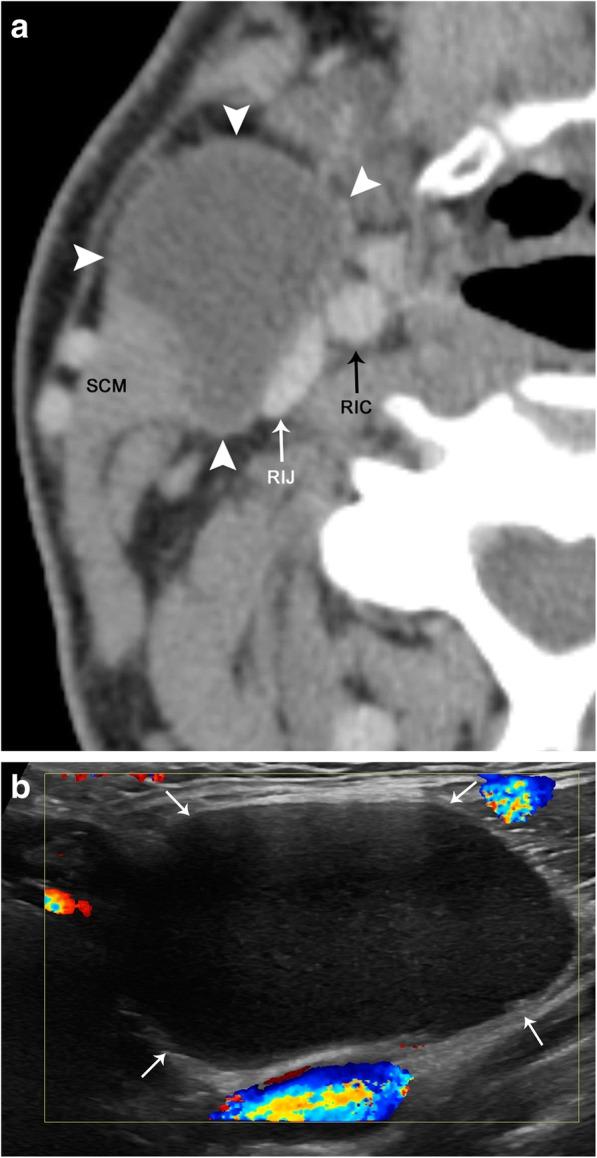

The complex anatomy of the carotid space within a small confined area is unique to the head and neck and allows for a vast array of pathology. This paper will review the anatomy of the carotid space from the skull base to the thorax, defining its borders at multiple levels, as well as its contents. The paper will also describe the myriad of mass lesions and vascular pathologies that may occur within the carotid space. The discussion will include anatomic considerations in differential diagnoses, imaging features, and lesion characteristics across multiple imaging modalities including CT, MRI, ultrasound, and conventional angiography. Entities discussed include paragangliomas, nerve sheath tumors, meningioma, fibromuscular dysplasia, carotidynia, thrombus, dissection, pseudoaneurysm, and pathology of the deep cervical chain lymph nodes. Understanding the complex and unique anatomy of the carotid space, as well as the nuances of navigating a broad differential, will empower the reader to make an accurate diagnosis.

在狭小受限区域内,颈动脉间隙复杂的解剖结构是头颈部所特有的,且会引发大量病变。本文将回顾从颅底到胸部的颈动脉间隙解剖结构,界定其在多个层面的边界及其内容物。本文还将描述可能出现在颈动脉间隙内的众多肿块性病变和血管病变。讨论将包括鉴别诊断中的解剖学考量、多种成像方式(包括CT、MRI、超声和传统血管造影)的成像特征及病变特点。所讨论的疾病包括副神经节瘤、神经鞘瘤、脑膜瘤、纤维肌发育不良、颈动脉痛、血栓、夹层、假性动脉瘤以及颈深链淋巴结病变。了解颈动脉间隙复杂独特的解剖结构以及鉴别广泛病变的细微差别,将使读者能够做出准确诊断。